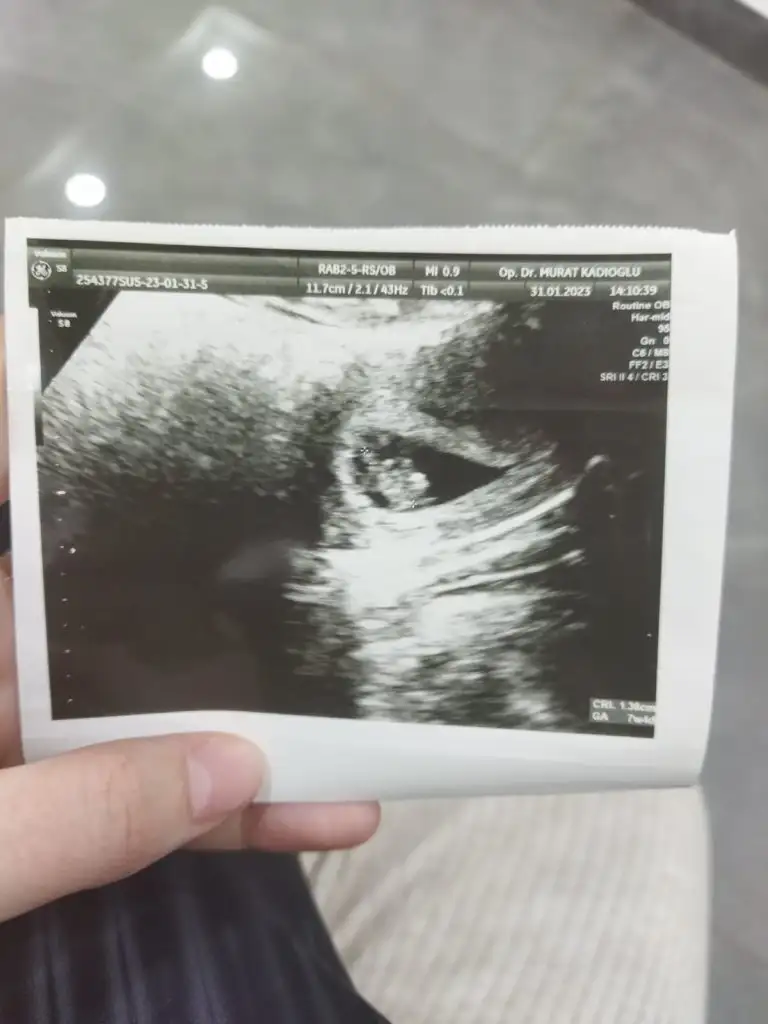

Plasentanın sağında duruyor bebek canım erkek sanki teoriyi doğruluyor eğer o parlaklık plasenta ise ve karından saEki Görüntüle 3388646 Eki Görüntüle 3388647 İgaleriden bi bunu bulabildim o erkekti ikinci fotoğrafta şimdi ki bebem

Karından mı ilk resim canımBak mesela ilk foto oğlumun ilk ulturoson resmiydi ikincisi simdikinin ilk kese fotoğrafi

İlk resim karından ikinci resim vajinalKarından mı ilk resim canım

Hepsi karından cnmKarından mı ilk resim canım

Plasentanın sağında duruyor bebek canım erkek sanki teoriyi doğruluyor eğer o parlaklık plasenta ise ve karından sa

Benimki karından ultrason. İlkin sagdaydi şimdi ortada ne olur acaba ? Görsel atamıyorumBence de erkek